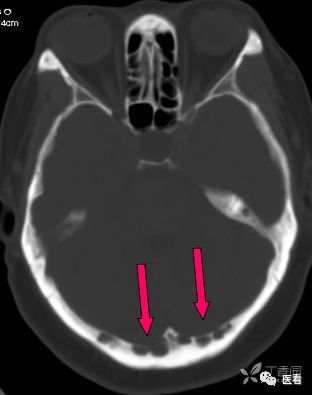

亨氏暗区

颅底(致密)骨产生的横行或放射状伪影,与设备性能也有关系

下图为16拍MSCT,伪影较轻。

此图为双排螺旋 CT图像, 伪影较16层及以上MSCT显著的多。